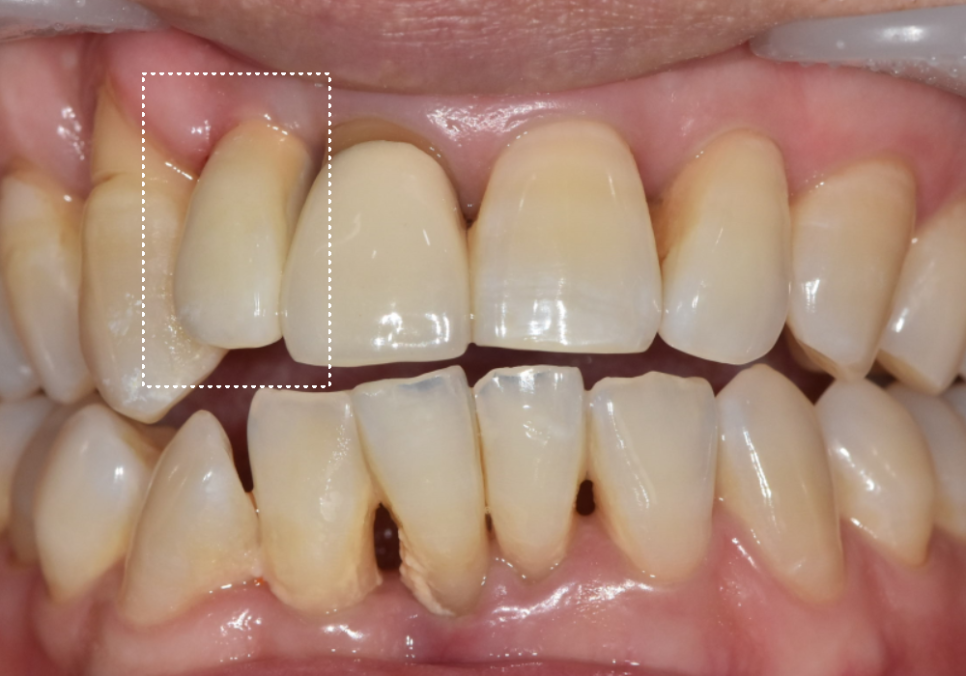

기존에 치료했던 오른쪽 앞니(#12)와

새로 임플란트를 심은 중앙 앞니(#11)가

자연스럽게 조화를 이루도록

보철을 제작해드렸는데요~

막상 보철물을 끼워보니 환자분께서

치아 길이가 약간 짧아 보이는 것 같다고

말씀하셨어요.

260312

사실 치아 길이는 0.5mm만 차이가 나도

사람의 인상을 좌우할 만큼 예민한 부분인 만큼,

치아의 모양이나 길이는

옆 치아의 영향을 많이 받는 상대적인 영역이에요.

이전에 임플란트를 했던

오른쪽 앞니가 살짝 길다 보니,

중앙 앞니가 상대적으로 짧아 보였던 것이죠.